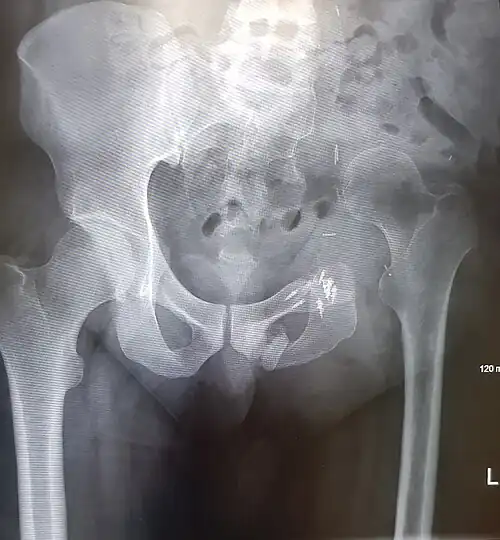

- An x-ray of a limb-sparing hemipelvectomy on the left side of a male pelvis taken one month after surgery.

- An x-ray of the same pelvis taken eighteen months after surgery highlighting the femur migration to its final resting place.